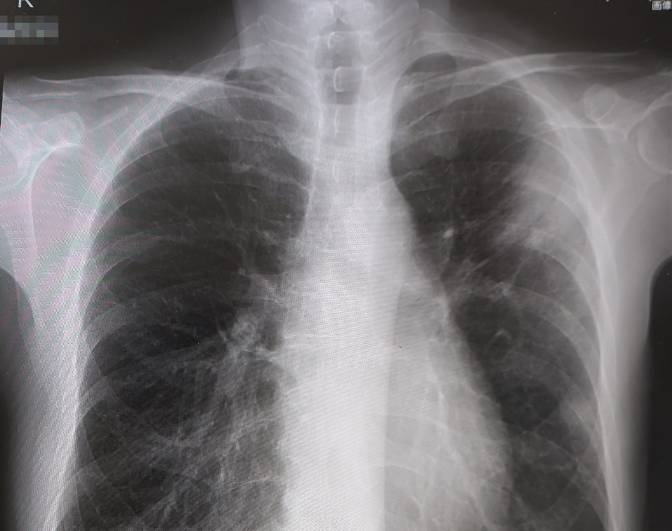

左肺の上部に白い影が映っていました。

背中の痛みの原因がこれだと分かりました。

レントゲンでは白い影がまだ残っていましたが、徐々に消えるそうです。

誤嚥性肺炎は肺の下部に影が出るのが一般的だそうです。

私の場合は、肺の上部だったため、別の原因が考えられました。